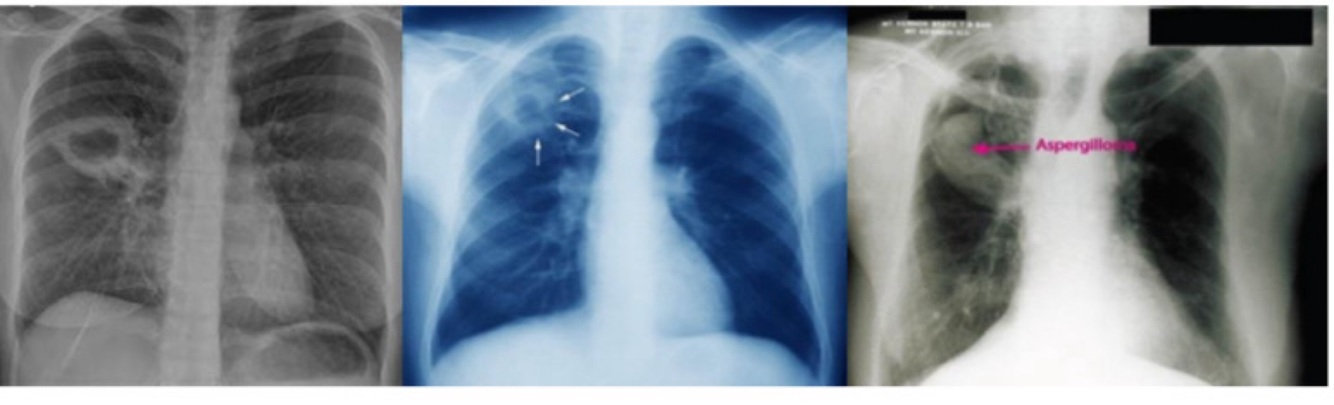

-RX: infiltrado persistente (>2 semanas) + linfonodomegalia hilar ipsilateral.

TB PÓS-PRIMÁRIA – bacilífera :

•Adolescente/adulto – reativação ou reinfecção

•Tosse prolongada, febre vespertina, sudorese noturna, perda de peso

•RX: infiltrado + cavitação

•Complicação: Aspergiloma (bola fúngica)